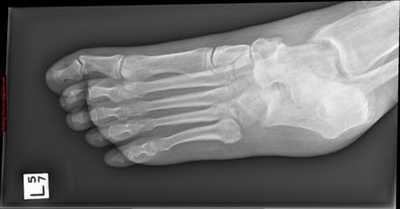

Рентгенологическое исследование

Для диагностики повреждения сустава Шопара делают рентген, КТ и МРТ. На передне-задней рентгенограмме определяют величину пяточно-кубовидного угла. Проводят одну касательную к наружному краю кубовидной кости и вторую касательную к наружному краю пяточной кости. В норме угол между касательными колеблется в пределах от 0 до 5°. Увеличение угла свидетельствует о нарушении стабильности пяточно-кубовидного сочленения. КТ во фронтальной и сагиттальной плоскостях позволяет выявить дефект суставных фасеток, смещение костей при вывихе и фрагментацию костей при переломе. КТ, по сравнению с рентгенографией, является более информативным методом диагностики. МРТ позволяет выявить дефекты отдельных связок.